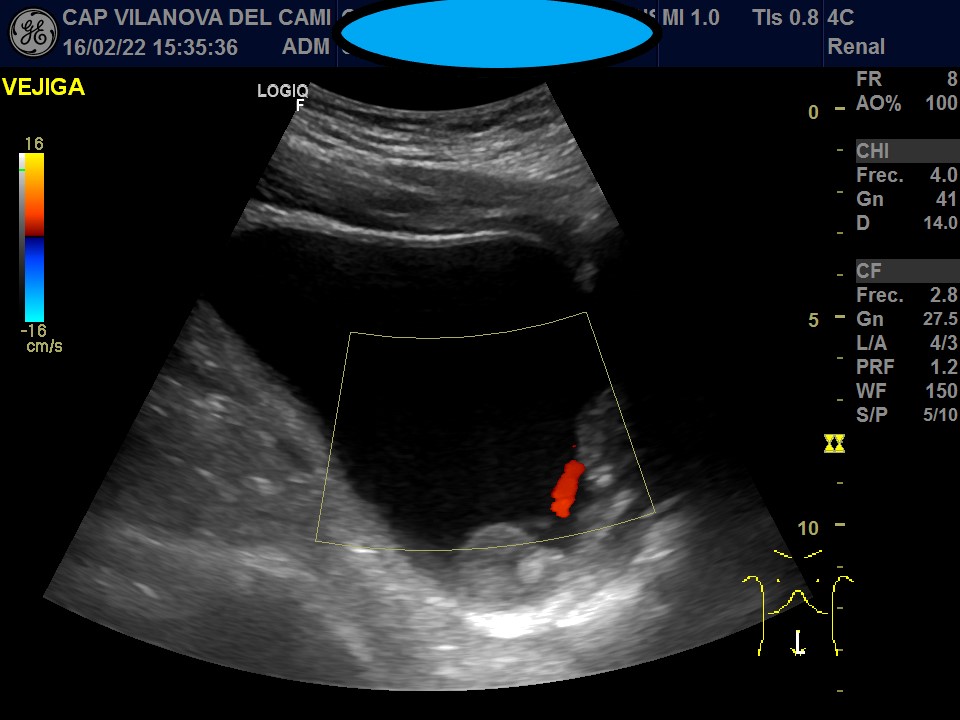

Vejiga urinaria bien distendida, de paredes engrosadas, con imágenes sugestivas de patología intraluminal y parietal. Neoformación irregular en pared posterolateral izquierda y suelo pélvico, que respeta el trígono vesical y la salida del meato ureteral, con captación Doppler color y algunas imágenes hiperecogénicas sugestivas de calcificación en su interior.